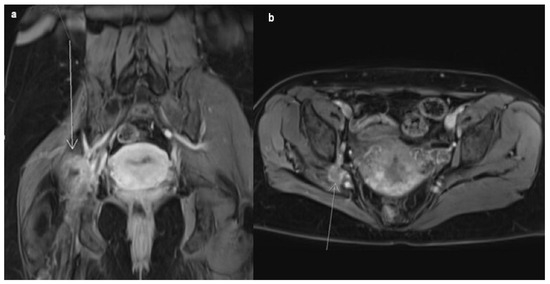

A 45-year-old female patient came to see a general practitioner because of a three-year-long mild and now exacerbating pain in her right leg, accompanied by a tingling sensation. She experienced weakness in her right leg and even more so in her right foot, with difficulty walking, which has now disrupted her daily life. Occasionally, in between regular menstrual bleedings that occurred every 28 days, she had been experiencing mild, 10-day-long extra-cyclical bleeding. Based on the presented symptoms, the patient was further examined by a neurologist, orthopedist, gynecologist, and neurosurgeon. The pain was first localized in the right gluteal region and then further spread through the posterior compartment of the whole leg. As mentioned, the pain was accompanied by upper-thigh tingling that also progressed downward to the foot. Assessing muscle strength during neurological examination, muscles on the right lower limb were found to be discretely weaker but able to contract and provide resistance. Moreover, when maximum resistance was exerted, the muscles were unable to maintain the contraction (graded 4+/5 muscle strength). The orthopedist’s examination yielded no noteworthy findings. The only gynecological symptom reported by the patient was intermenstrual bleeding. In terms of extra-cyclical bleeding, all diagnostic procedures were carried out in order to find the possible organic cause. Examinations of the patient’s hormonal status were also carried out. All findings were within physiological limits and ruled out the existence of organic and hormonal causes of intermenstrual bleeding, i.e., the existence of endometrial polyps, cervical polyps, submucosal myomas, and colposcopic lesions that can bleed, but also hormonal-cause and abnormal uterine bleeding in the middle of the cycle. Furthermore, the gynecologist reported normal results from the Pap smear and colposcopy. Transvaginal color Doppler ultrasound showed a uterus in a marked retroverted (RVF) position with inhomogeneous and irregular contours; showed multiple non-cavity-distorting myomas in its anterior wall, up to 5 cm in size; and ruled out the existence of lesions on the genital organs that could raise suspicion of pelvic endometriosis. The pain sensitivity of the tissue of the uterus, parametrium, and adnexal region was not determined by pelvic examination. All tumor markers (cancer antigen 125, carcinoembryonic antigen, cancer antigen 19.9), as well as inflammation markers (c-reactive protein, erythrocyte sedimentation rate), were within reference values. Therefore, magnetic resonance imaging (MRI) of the small pelvis was advised. Examination was performed using a 1.5-T scanner (Avanto fit, Siemens Medical Systems, Erlangen, Germany) with a master gradient system (45 mT/mpeak gradient amplitude, 200 m/T/s slew rate) and an eighteen-element array body surface coil and thirty-two element spine coil. The bladder with perivesical adipose tissue, the lineages of both ovaries, the parametrium with ischiorectal fossae, as well as the visible digestive tract and mesorectal and pararectal adipose tissue, were morphologically preserved, without any hiperintense solid or cystic endometriosis-like mass lesions. The body of the uterus was clearly demarcated by several intramural fibroids, with the largest one being the right anterior wall, measuring approximately 5 cm. None of the identified alterations has the potential to elucidate the neurological or gynecological symptoms observed in our patient. A minimal amount of free fluid was visible in the pelvis. It could be seen that the right gluteal group of muscles was atrophic, as in the right external obturator muscle compartment, and a vaguely demarcated heterogeneous formation was registered, transversely measuring approximately 30 mm and heterogeneously increasing the signal intensity post contrast. The whole formation was vaguely demarcated from the neurovascular pedicle, hence preventing the exclusion of the potential presence of an infiltrative lesion with an unknown cause (Figure 1).

Figure 1. Postcontrast coronal (a) and axial (b) T1w FS MRI images present a heterogeneous mass in the right obturator fossa (white arrows), vaguely demarcated from the neurovascular pedicle. Note the large fibroids in the anterior uterine wall (picture (b)).